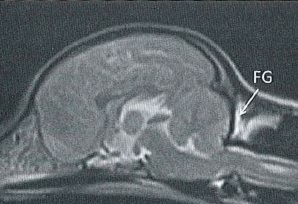

They

hypothesized that there may be insufficient room within the skull for

the forebrain, and that may contribute to backward displacement and

overcrowding of the hindbrain. They focused upon the forebrain's

olfactory bulb (OB -- also called olfactory lobe), which is at the lower front of the forebrain and

directly behind the olfactory receptor cells in the dog's nose. The more brachycephalic (short-muzzled) the dog, the

more the OB tends to be lower and the more the frontal lobe tends to be

flattened against the front of the skull. (Compare the normal

location of the canine forebrain in the diagram at the left, with the

flattened frontal lobe and the lower olfactory lobe of a CM/SM-affected

cavalier, at the right.)